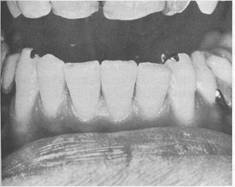

6-24). Incisal rests are used predominantly as auxiliary rests or as indirect retainers.

Although the incisal rest may be used on a canine abutment in either arch, it is more applicable to the mandibular canine. This type

of rest provides definite support with relatively little loss of tooth structure and little display of metal. Esthetically it is preferable to the three­quarter crown (Fig. 6-25). The same criteria apply in deciding whether to use unprotected enamel for an occlusal rest on a molar or premolar. An incisal rest is more likely to lead to some orthodontic movement of the tooth because of unfavorable leverage factors than is a lingual rest.